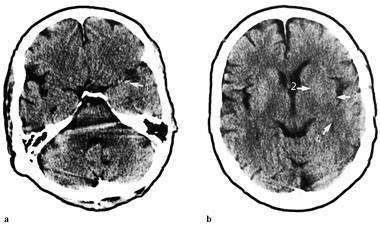

Hos pasienter med alvorlig slag (SSS-skåre 8) varierte antallet tidlige infarkttegn mellom null og fem. Hos to pasienter med lett slag (SSS-skåre 42 og 46 og CT 322 og 324 minutter etter sykdomsstart) hadde én pasient fire tidlige infarkttegn og én ingen. Hos to pasienter med alvorlig slag (SSS-skåre 8 og 10 og CT 120 og 130 minutter etter sykdomsstart) hadde én pasient fem tidlige infarkttegn og én ett. Hos to pasienter med alvorlig slag og CT to timer etter sykdomsstart hadde den ene ikke infarkttegn mens den andre hadde fire (fig 1).